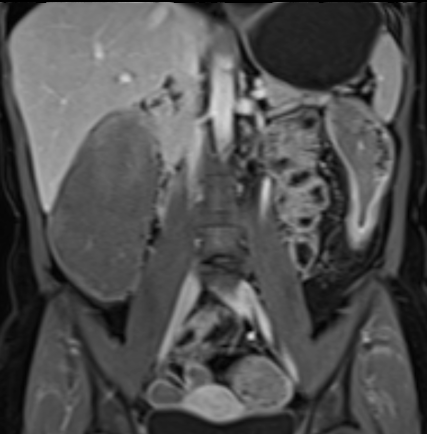

Bệnh nhân nữ 48 tuổi, đang điều trị bằng thuốc kháng TNF, được chỉ định nội soi đại tràng.

Phát hiện hẹp lòng ruột ở đại tràng sigma, không thể vượt qua được khi nội soi.

MR-enterography được thực hiện để đánh giá mức độ lan rộng của chỗ hẹp.

Cuộn qua các hình ảnh.

Ruột non bình thường, nhưng ghi nhận các đoạn hẹp ở đại tràng xuống và đại tràng ngang.

Cả hai đoạn hẹp đều có thành ruột dày đến 8 mm và ngấm thuốc rõ rệt theo kiểu niêm mạc ở đại tràng xuống và kiểu phân lớp ở đại tràng ngang.

Giãn ruột trước chỗ hẹp được ghi nhận ở cả hai đoạn.

Do các chỗ hẹp này không hiện diện khi nội soi đại tràng trước khi điều trị kháng TNF, nhiều khả năng chúng đã hình thành trong quá trình điều trị.

Do đó, quyết định phẫu thuật cắt đại tràng gần toàn bộ với miệng nối hồi-sigma đã được đưa ra.